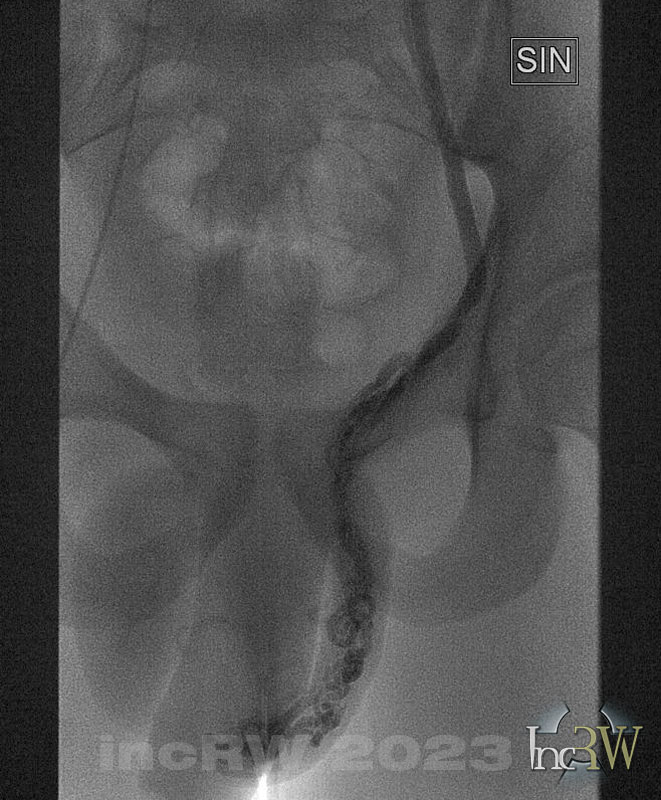

- Innan man går ner med mikrokateter selektivt i v.spermatica köres kontrastserier från Glidcath-katetern med kontrastinjektorn (5-7ml, 5-7ml/s).

I många fall delar sig v.spermatica halvvägs ner mot pungen i 2 eller fler kärlgrenar.

Patienten behöver krysta i samband med kontrastserierna för att fylla kontrast ner dist i v.spermatica. - Generellt bör man emboliser så distalt som möjligt då det venösa återflödet från testis oftast även går till iliaka interna venen.

Det kan även finnas mindre återflöden via femoralis venen men dessa små vener åtgärdas inte. - Finns där en proximal delning får man coila båda grenarna.

Finns en distal förgrening kan coils läggas innan delningen. - Med mikrokateter går man ner distalt i v.spermatica som anses i första hand orsaka varicerna.

- Kontrastserier körs för hand (3ml spruta) eller med injektor (3ml. 3ml/s) i mikrokatetern när denna ligger mer distalt iv.spermatica. Patienten krystar!